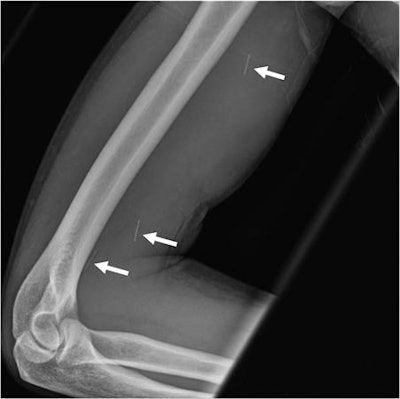

The study revealed a high rate of complications, ranging from symptoms caused by intravenous injections to respiratory issues and back pain. The most frequent complications were related to the skin and soft tissues and were caused by the use of nonsterile needles, Flores said.

"In some cases, we found septic emboli in the lung or brain," Flores said in a statement released by the RSNA. "As these patients start having to access larger veins, they become more prone to these types of infections."